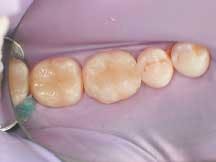

After applying the dentin material, the clinician placed a .5 mm layer of medium value enamel material, followed by the final layer of clear transenamel material, using the same buildup and curing technique as specified for the dentin layers. A final cure of each restoration was performed from the occlusal aspect for 30 to 40 seconds per tooth (Figure 4).

The interproximal areas were verified with floss and, in areas where any flash existed, a 12-B blade was used at the gingival margin in a gentle, carving motion to remove it (Figure 5). To reproduce the natural shape and anatomy of the teeth, a series of fine and super-fine diamond finishing burs (Axis Dental Corporation) were used. The occlusion was then checked and, where necessary, a pointed bur was used to reform the anatomy following any occlusal adjustments.

The rubber dam was removed, occlusion was checked and adjusted, and final polishing was completed using a green Jiffy polishing cup (Ultradent Products, Inc.) and Jiffy bristle brush. To best polish the gingival areas, a finishing strip (Epitex Strip) was used. Figure 6 shows the completed direct composite posterior restorations.

4

5

6